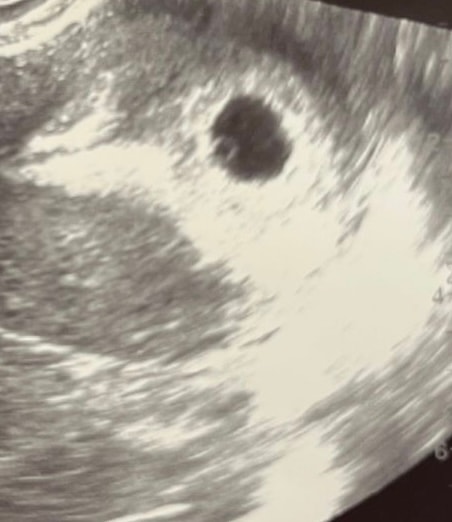

Нашли ПЯ и ЖМ , сегодня 21 дпп .

кто-нибудь видит кольцо с бриллиантом ? Мне сказали примерно так должно выглядеть